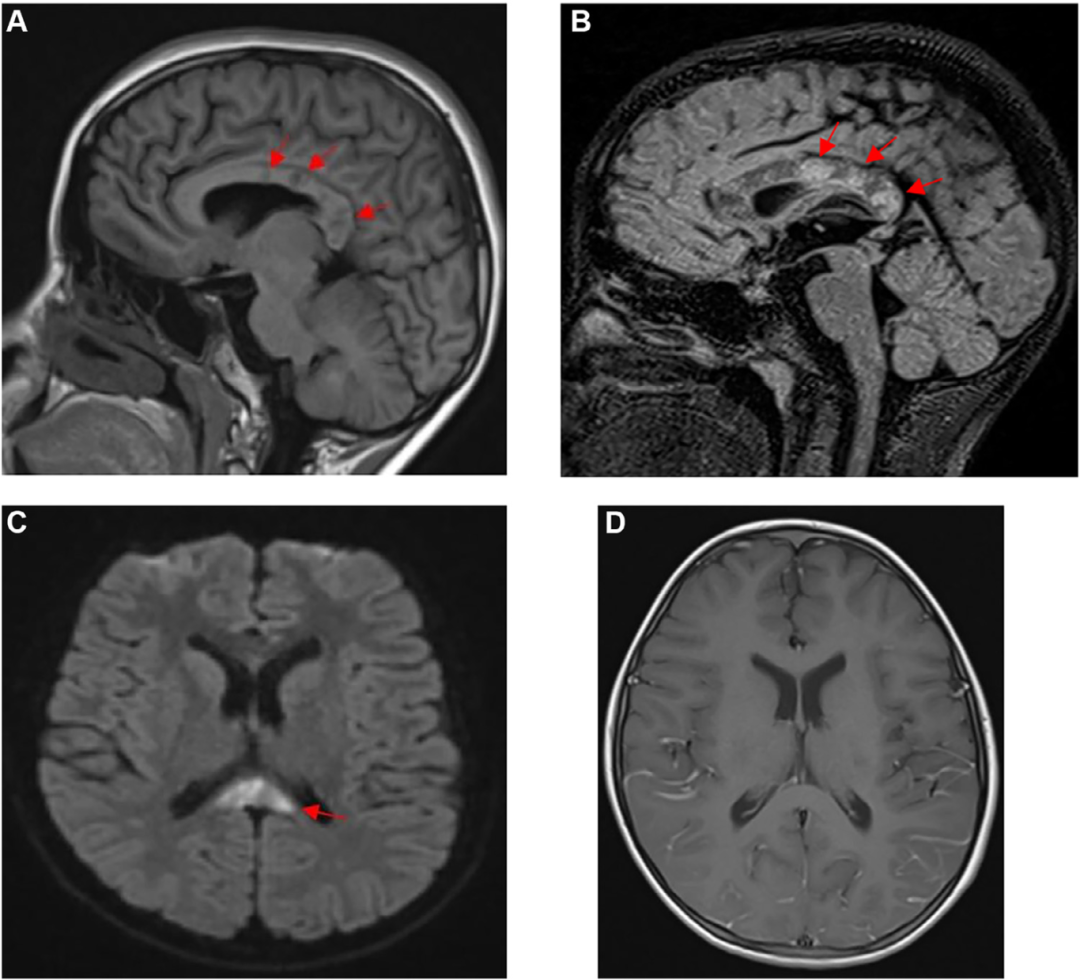

鉴于患者的神经系统状态,立即进行脑部MRI检查(图1),结果显示多个结节样信号异常,主要累及胼胝体中央部及幕上皮质下白质。这些异常在T1加权图像上呈低信号,在T2加权和FLAIR序列上呈高信号,扩散受限,钆造影后未见强化,

图1

这些MRI表现强烈提示Susac综合征。